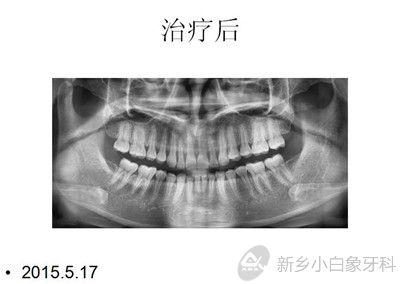

结束时间:2015年5月17日

下图为治疗前后图片资料: